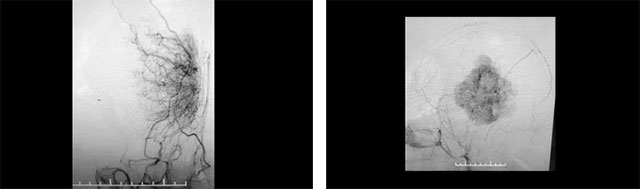

▲ 腫瘤病灶血供豐富

沈建康教授團隊首先為患者進一步完善檢查,頭顱MRI增強檢查顯示,患者左側(cè)顳頂葉部位的腫瘤約為6.3cm×4.4cm×6.7cm,體積巨大。經(jīng)行DSA檢查發(fā)現(xiàn),腫瘤包裹纏繞多根重要的動脈血管,血供非常豐富。盡管切除難度高,手術(shù)風(fēng)險大,但綜合分析考慮腫瘤為腦膜瘤,系良性腫瘤,手術(shù)成功可以治療好。

圍繞這一棘手情況,沈教授團隊聯(lián)合醫(yī)院腦血管病科主任張琪博士,開展了嚴(yán)謹(jǐn)?shù)脑u估討論,以確定治療方案。臨床經(jīng)驗豐富的沈建康教授指出,顳頂葉部位巨大腦膜瘤,治療方法為手術(shù)切除,患者手術(shù)指征明確,未見明顯手術(shù)禁忌。由于該腫瘤有明顯的頸外動脈供血,討論后考慮采取“術(shù)前栓塞+腫瘤切除”的手術(shù)方案,以減少術(shù)中出血,利于腫瘤分塊切除,盡可能避免意外發(fā)生。

術(shù)前,沈教授團隊向胡女士家屬充分溝通、明確手術(shù)的必要性和風(fēng)險性,并獲得充分理解、簽字同意后開始手術(shù)。借助先進的雙C臂FD20/20雙向血管造影系統(tǒng)DSA,先由張琪博士為患者行經(jīng)導(dǎo)管頸外動脈供血血管栓塞術(shù),腦血管造影顯示,患者腫瘤供血動脈主要由左側(cè)腦膜中動脈、顳淺動脈及左側(cè)大腦后動脈腦膜支參與。張琪博士在DSA引導(dǎo)下分步完善栓塞供血動脈,直至完全切斷腫瘤的主要供血,為沈建康教授進行腫瘤切除創(chuàng)造了有利條件。